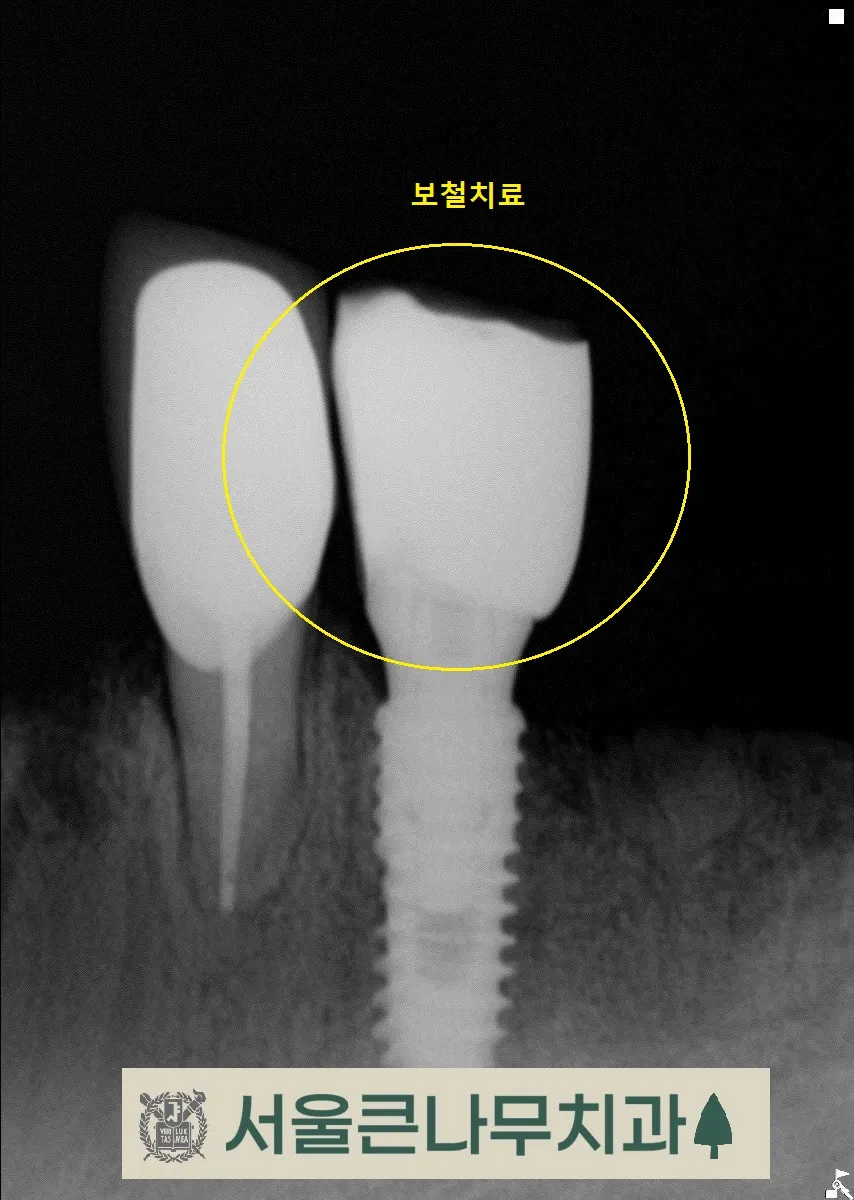

임플란트가 뼈와 잘 붙을 때까지 기다린후 본을 떠 임플란트위에 보철을 올려줍니다.

아래턱

윗턱

여러번의 과정을 거쳐 위턱, 아래턱의 보철을 올려 완성해주었습니다.